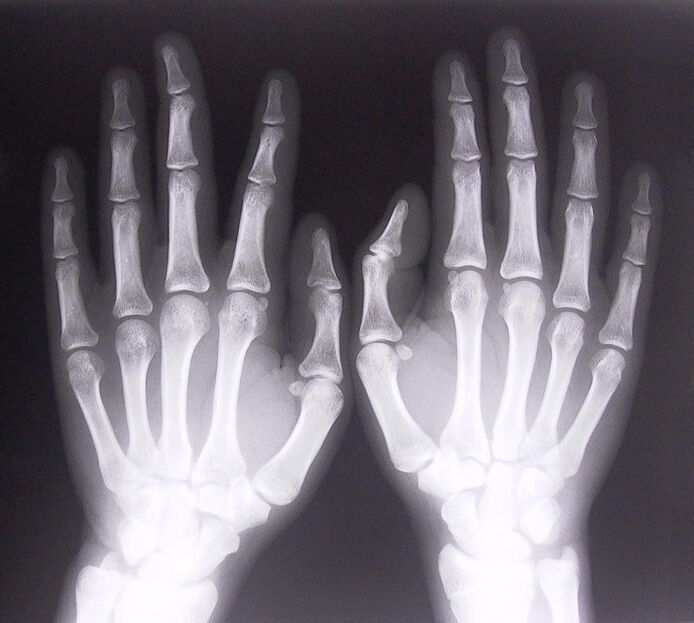

- Tehke röntgenikiirgus.

- Stenoseeriv ligamentiit. Haiguse põhjuse kindlakstegemiseks on vaja läbida röntgenuuring. Sümptomid on tüüpilised: käe valulik liigutamine, kokkusurutud peopesa silmus. Samuti kostub pikendamise ajal tavaliselt klõpse.